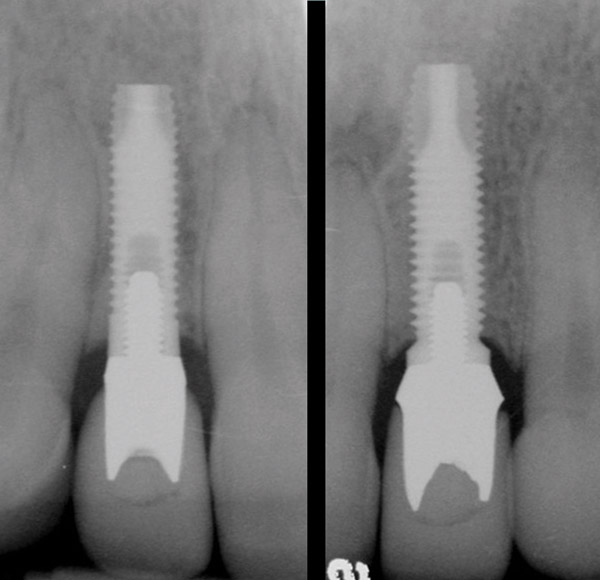

Figure 11  Periapical radiograph at the time of provisionalization. Note the wide peak of bone between implants Nos. 8 and 9.

Figure 11

Figure 14  Initial periapical radiograph revealed internal root resorption of teeth Nos. 8 and 9 with almost complete horizontal severing of the crowns from the roots.

Figure 14